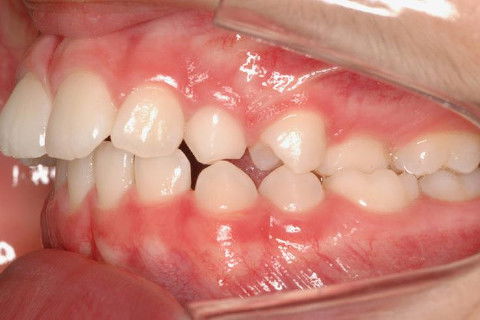

LATERAL ESQ. INICIAL

PACIENTE CLASSE II.

ATRESIA DE MAXILA.

SOBREMORDIDA.